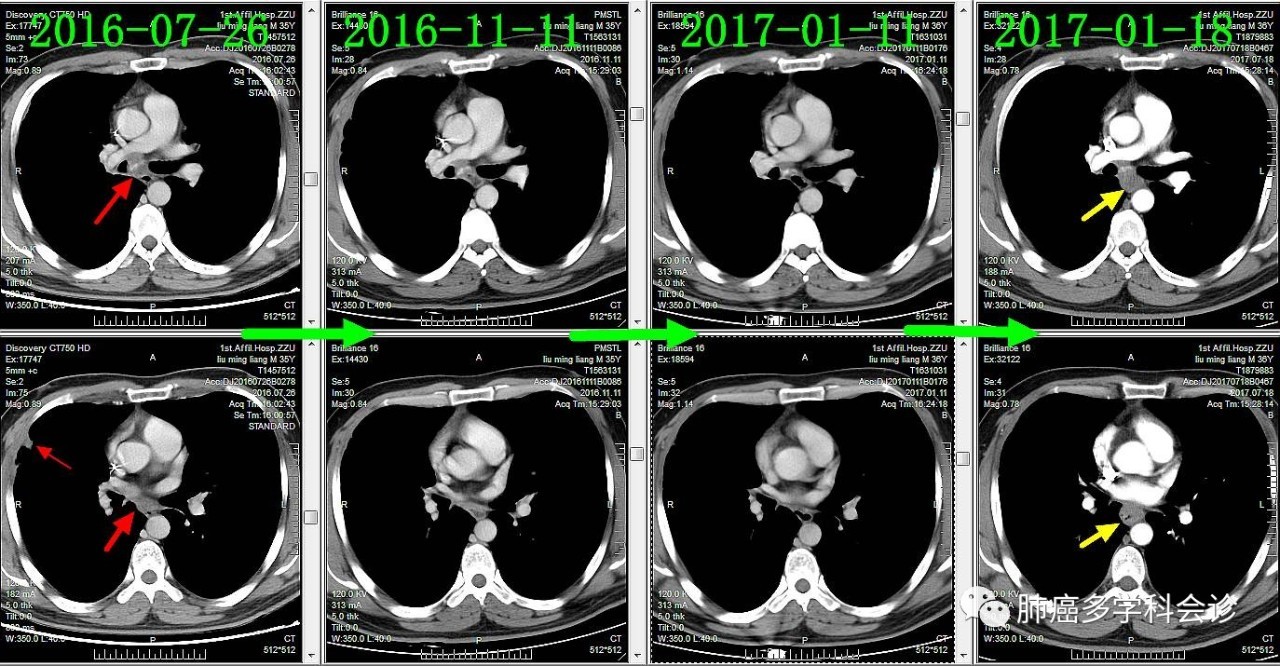

下面通过对比治疗过程中胸部CT变化,展示胸部肿瘤此消彼长的过程:

肺原发灶略有缩小

纵隔肿大淋巴结逐渐缩小

胸膜转移灶消失

食管转移灶从小到大

食管不是肺癌的常见转移部位,容易被忽视。回顾该患者以往的胸部 CT 可见:在纵隔淋巴和原发灶逐渐退缩过程中,食管转移却逆势发展起来,反映了肿瘤对治疗反应的异质性。